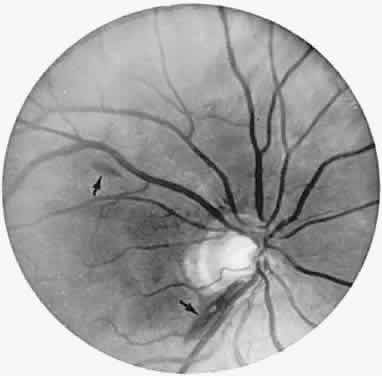

The retinal variety may be admixed in a person who suffers the more conventional attacks of migraine. It is presumed that vasospasm in the retinal circulation determines transient hypoxia, perhaps somewhat similar to the visual cortical event. On rare occasions, the fundus has been examined during typical retinal migraine episodes, and arterial constriction has been described. Wolter and Burchfield106 photographically documented such an episode and demonstrated mild “retinal edema”; vessel narrowing is also evident (Fig. 8). Fortunately, permanent complications of retinal migraine are rare. These may take the form of central retinal artery occlusion or ischemic papillopathy (see Volume 2, Chapter 16); nerve fiber bundle visual field defects may be demonstrated (Fig. 9).

Fig. 8. Retinal migraine. A. During amaurotic episode. Note the dusky appearance of the fundus, increased retinal sheen (possibly edema), and dark narrowed veins (arrows). The disc is also hyperemic. B. Fundus after episode. Compare paired arrows. (Courtesy of Dr. J. Reimer Wolter)

Fig. 9. An 18-year-old student with recurrent episodes of left retinal migraine. After a typical attack, he noted an inferior field defect. A. Fundus shows a defect in the superior arcuate nerve fiber bundle (between arrows: compare fiber layer below disc). B. Visual field defect corresponds to a retinal nerve fiber layer defect.